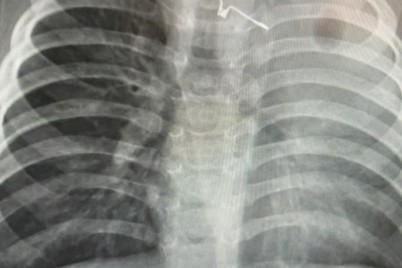

جدة - سلطان السلمي تمكّن فريق طبي جراحي بمستشفى الملك عبدالعزيز بجدة، من إزالة جسم غريب علق في مرئ...